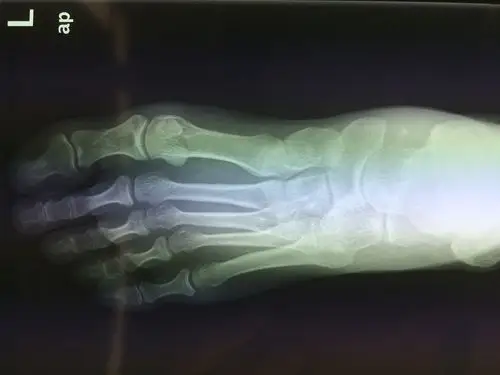

左足舟骨粉碎性骨折